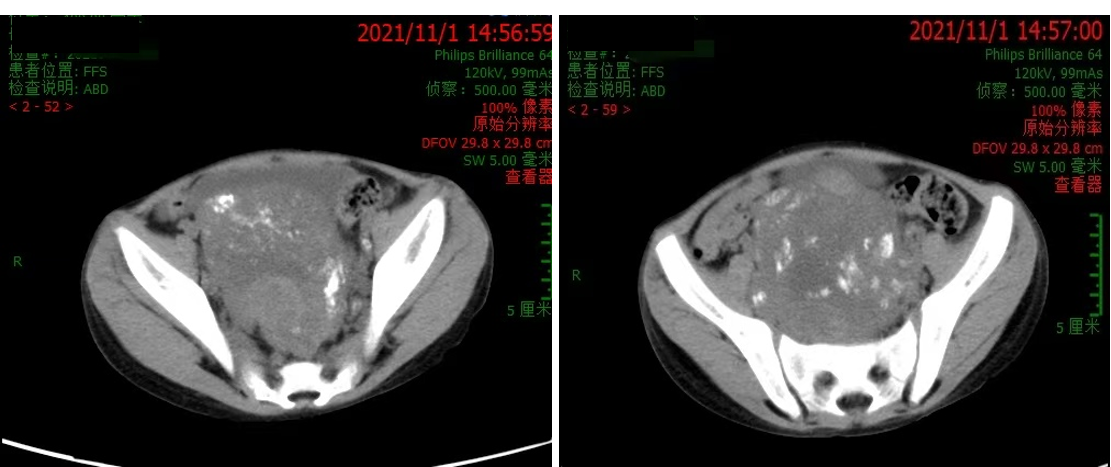

我院CT(2021.08.30):下腹部至盆腔内不规则混杂信号包块(约135.9mm×73.7mm×216.4mm),考虑神经母细胞瘤;骨盆、股骨上段及椎体骨质信号不均匀,不排除骨浸润;双肾输尿管积水。

2021.11.01 腹部CT:瘤灶较前减小(约97.2mm×63.8mm×174.3mm),双肾积水较前稍好转,骨盆及椎体骨质密度似欠均匀。